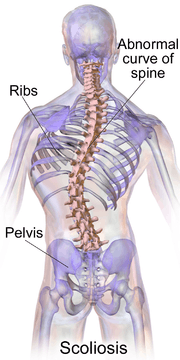

Scoliosis

| A drawing of scoliosis | |

Scoliosis is a medical condition in which a person's spine has a sideways curve.[2] The curve is usually "S" or "C" shaped.[2] In some the degree of curve is stable, while in others it increases over time. Mild scoliosis does not typically cause problems, while severe cases can interfere with breathing.[3][4] Pain is typically not present.[5]

Scoliosis is defined as a three-dimensional deviation in the axis of a person's spine[8] In the diagnostic sense it is defined as a spinal curvature of more than 10 degrees to the right or left as the examiner faces the person, i.e. in the coronal plane. Deformity may also exist to the front or back as the examiner looks at the person from the side, i.e. in the sagittal plane.